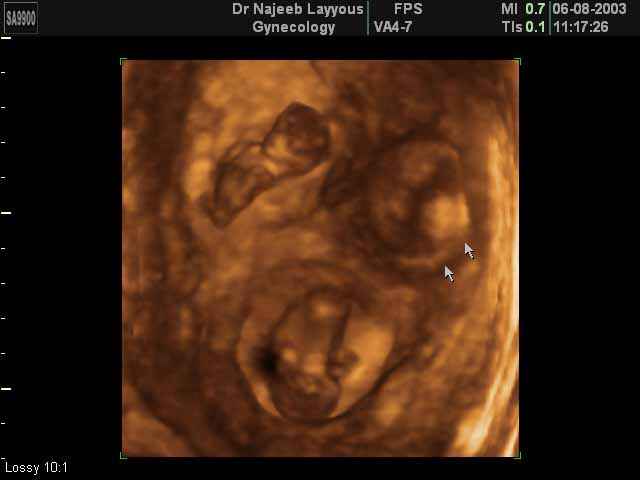

- Multiple Pregnancy Ultrasound Photos

- The Clinical Advantages of 3D and 4D Ultrasound

- Definition and Features of Four Dimensional Ultrasound

- Uses of 4D Ultrasound scan